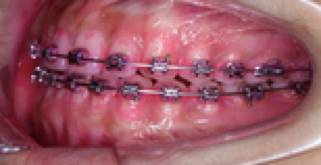

医生发现了我对刷牙的不在意,于是给我看了个实验——菌斑染色实验:

刷牙前

(红色部分是菌斑附着区,代表没刷干净)

用正畸专用声波震动牙刷刷牙后

(红色菌斑区域消失)